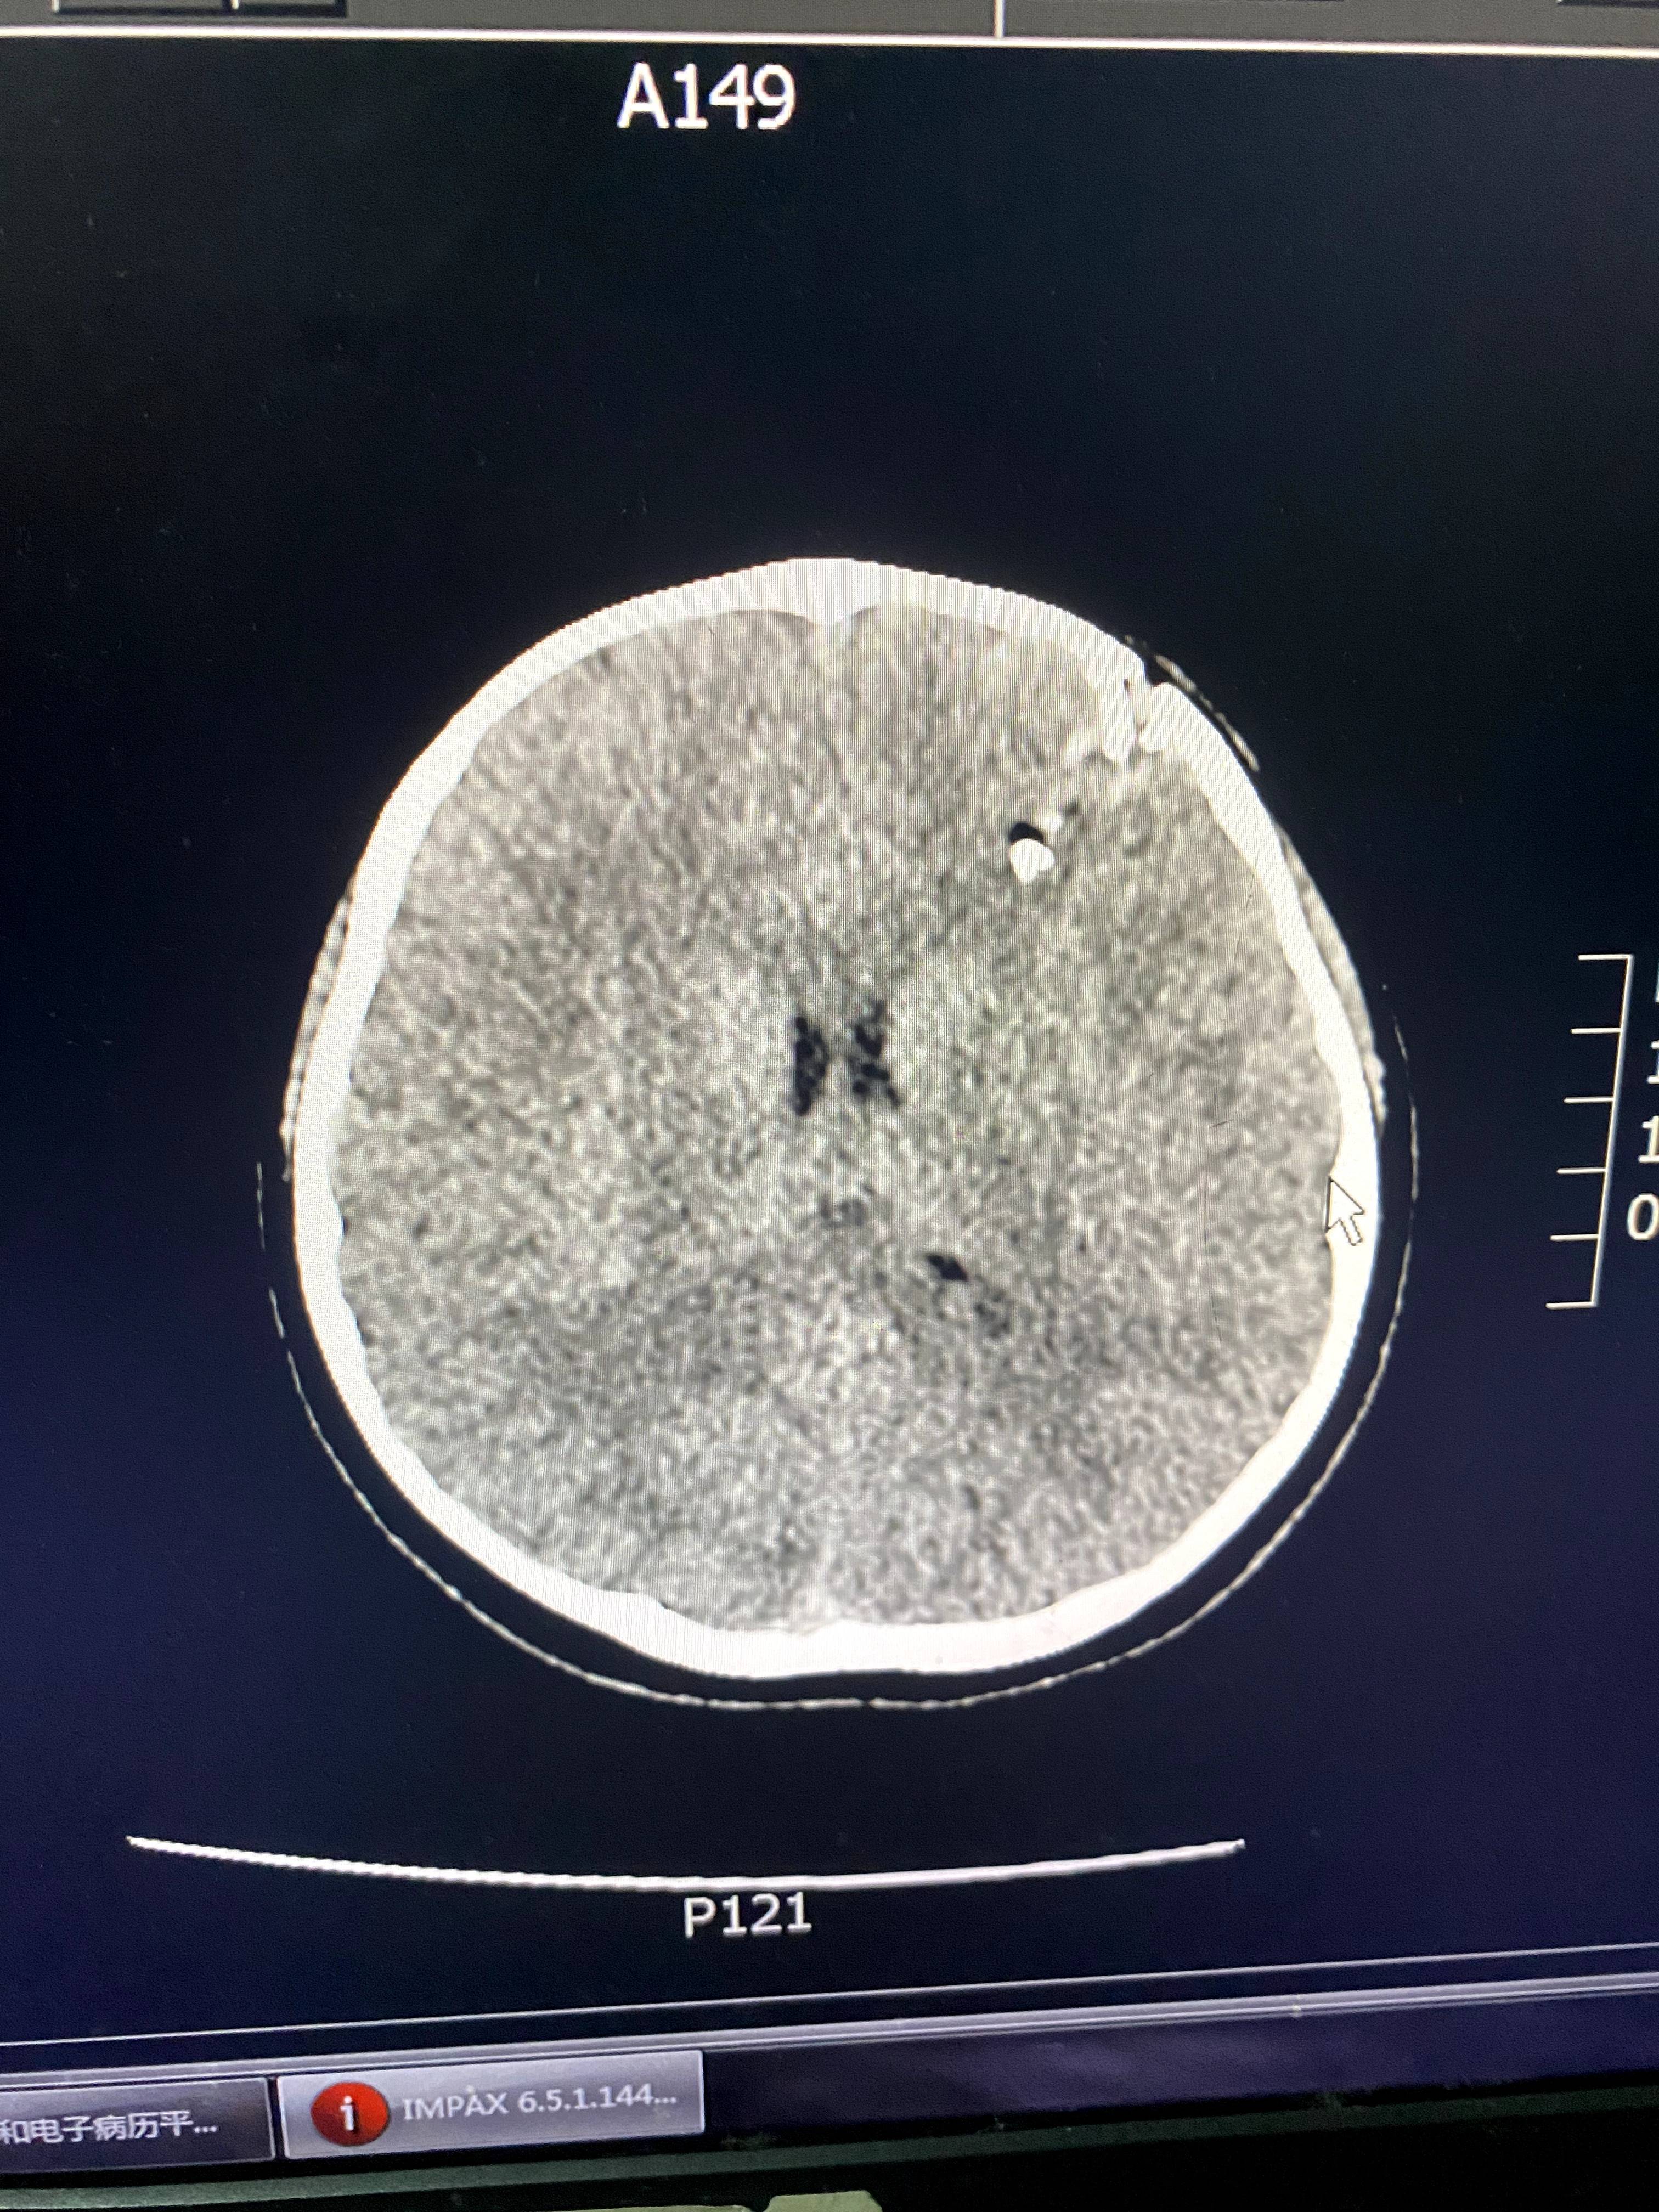

CT显示,星星的颅骨碎裂,颅内有异物。讲述者供图

班主任就站在孩子身边。郭洋还没来得及多问,医生就从CT室匆匆赶来,指着电脑上的片子告诉郭洋,“颅骨已经碎了,颅内疑似有异物,要马上做开颅手术。”郭洋说,女儿从小到大几乎没受过什么伤,连感冒都少。听到“开颅”两个字时,她“腿都吓软了”。

后来的伤情鉴定结果显示,星星的头面部软组织裂伤,开放性颅骨骨折伴硬脑膜破裂,颅内出血,颅内异物,脑挫裂伤,伤情构成重伤二级。这起事件当年引起了媒体的广泛关注,涉事老师被判处有期徒刑五年,并被禁止从事密切接触未成年人的工作。